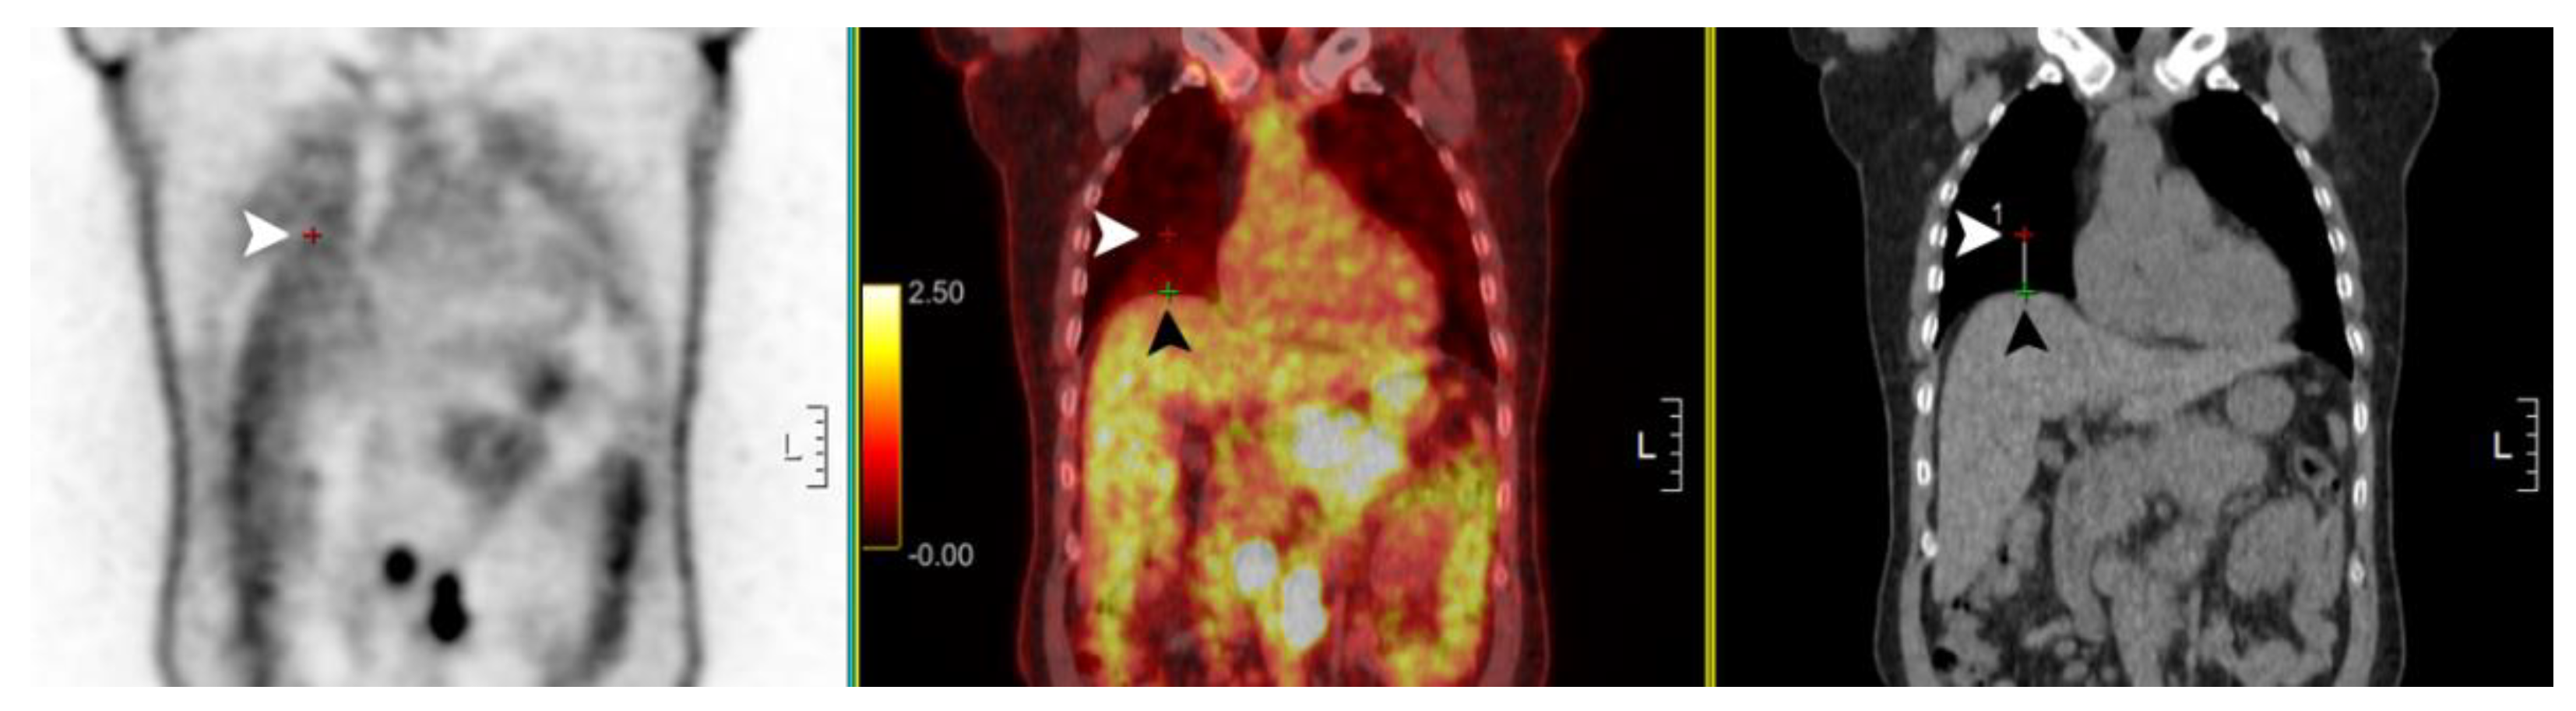

3. Results

| Reasons | Change of SUVmax (%) | n (%) | |

|---|---|---|---|

| Median | Range | ||

| [18F]FDG uptake outside the liver on CT in sPET/CT | 15% | [7% to 71%] | 4 (11%) |

| More blurring in sPET/CT | 11% | [−3% to 32%] | 6 (17%) |

| Unremarkable | 1% | [−8% to 18%] | 12 (34%) |

| More blurring in pPET/CT | −19% | [−30% to −8%] | 12 (34%) |

| [18F]FDG uptake outside the liver on CT in pPET/CT | −30% | [−30% to −30%] | 1 (3%) |

| Total patients | −4% | [−30% to 71%] | 35 (100%) |